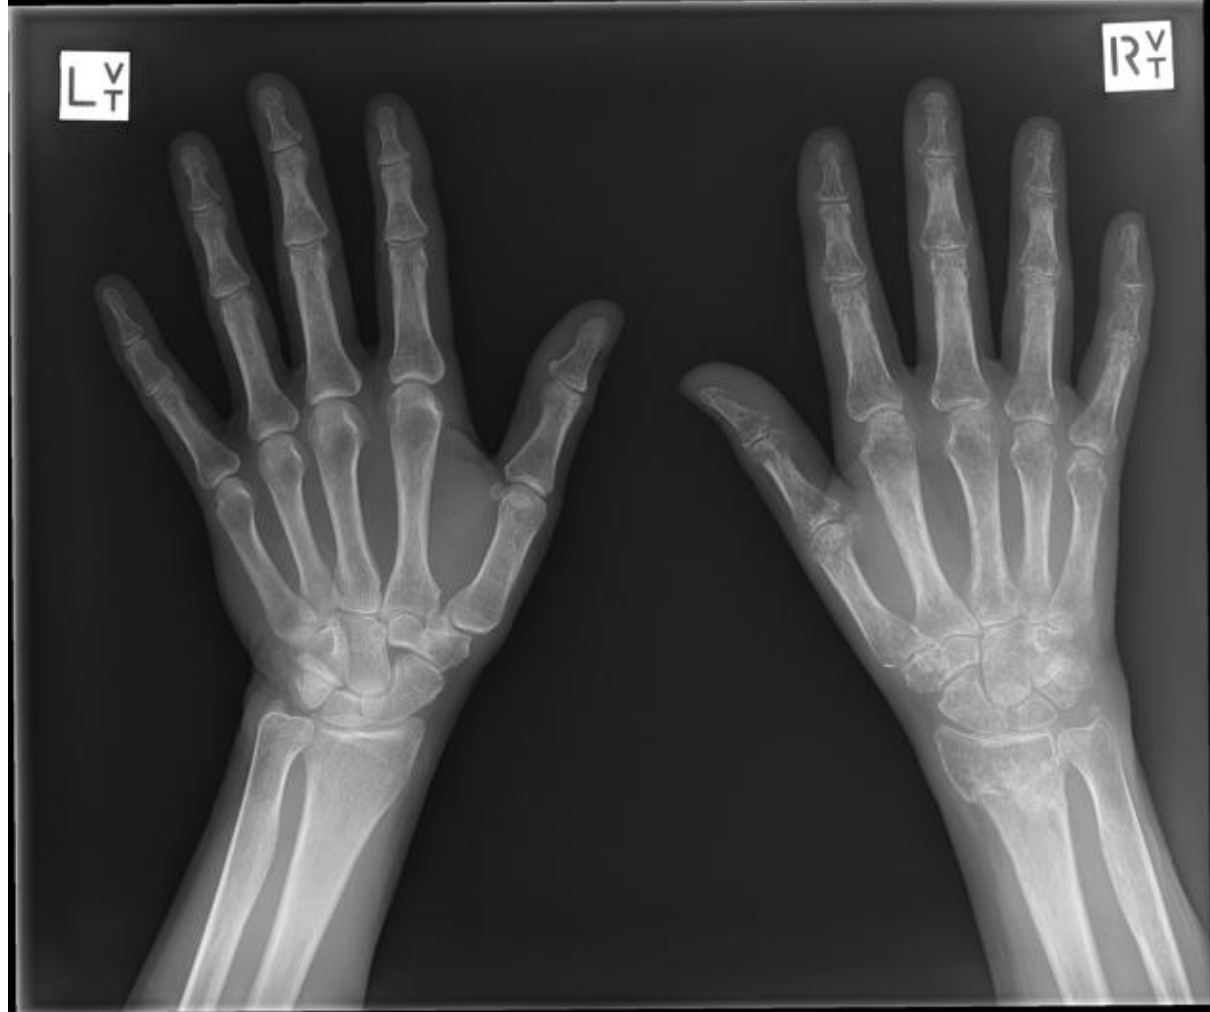

W pierwszej fazie nie ma typowego dla dawnego opisu Sudecka „plamistego odwapnienia” w RTG. Osteopenia plamista pojawia się często dopiero po kilku tygodniach – i nie może być wyczekiwana jako warunek rozpoznania.

- RTG wczesnej fazy często jest prawidłowe.